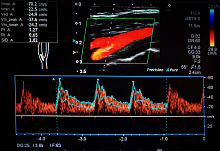

Сравнение транскатетерной и хирургической замены аортального клапана

Целью исследования PARTNER 3 было сравнить долгосрочную эффективность транскатетерной замены аортального клапана с хирургической заменой аортального клапана у пациентов с симптомным аортальным стенозом.